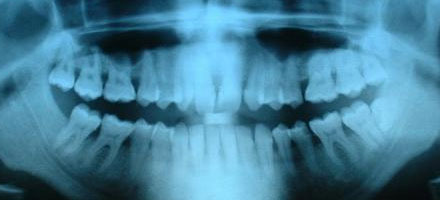

Wij vertegenwoordigen uitsluitend merken die een ruime ervaring hebben op het gebied van röntgentechnologie, waaronder Carestream Dental en Vatech. De meest geavanceerde OPG, RSP en Conebeam CT systemen zijn bij ons verkrijgbaar.